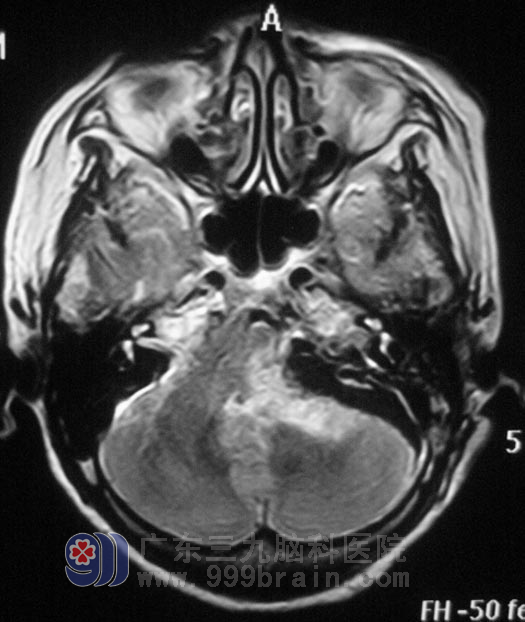

广东三九脑科医院头颅MR检查显示:左侧桥小脑角区示一不规则形囊实性占位性病变,增强后实性部分呈不均匀明显强化,囊性部分未见强化,侧面听神经增粗强化,范围约为3.6cm×4.2cm×3.7cm,周围示轻微水肿,桥脑、延髓,左侧桥臂及左侧小脑半球受压变形、移位,四脑室受压变窄,左侧内听道明显扩大。检查左耳失聪,左侧额纹、鼻唇沟较右侧轻微变浅,伸舌左偏。